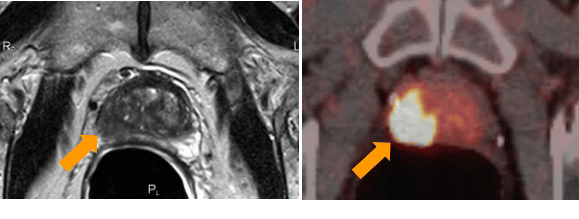

Direct detection of metastases in prostate cancer is achieved by PSMA-PET1 – a functional nuclear imaging method. PSMA refers to the prostate-specific membrane antigen found on prostate cancer cells. In PSMA-PET, a ligand labeled with a gallium68 atom binds to PSMA receptors and visualizes prostate cancer metastases.

The use of PSMA-PET in the primary diagnosis of prostate cancer is becoming increasingly important. For example, if a cancer site is found in the MRI scan, the primary diagnostic test for the prostate, it may be possible to confirm the site using PSMA-PET, and a biopsy may not be necessary prior to treatment. Also, the combination of MRI and PSMA-PET may allow a more accurate assessment of the aggressiveness of prostate cancer than the Gleason score of the biopsy (scientific studies are currently being conducted on this). A biopsy can then be performed in the same session as the treatment, i.e. intraoperatively, instead of before the carcinoma is treated.